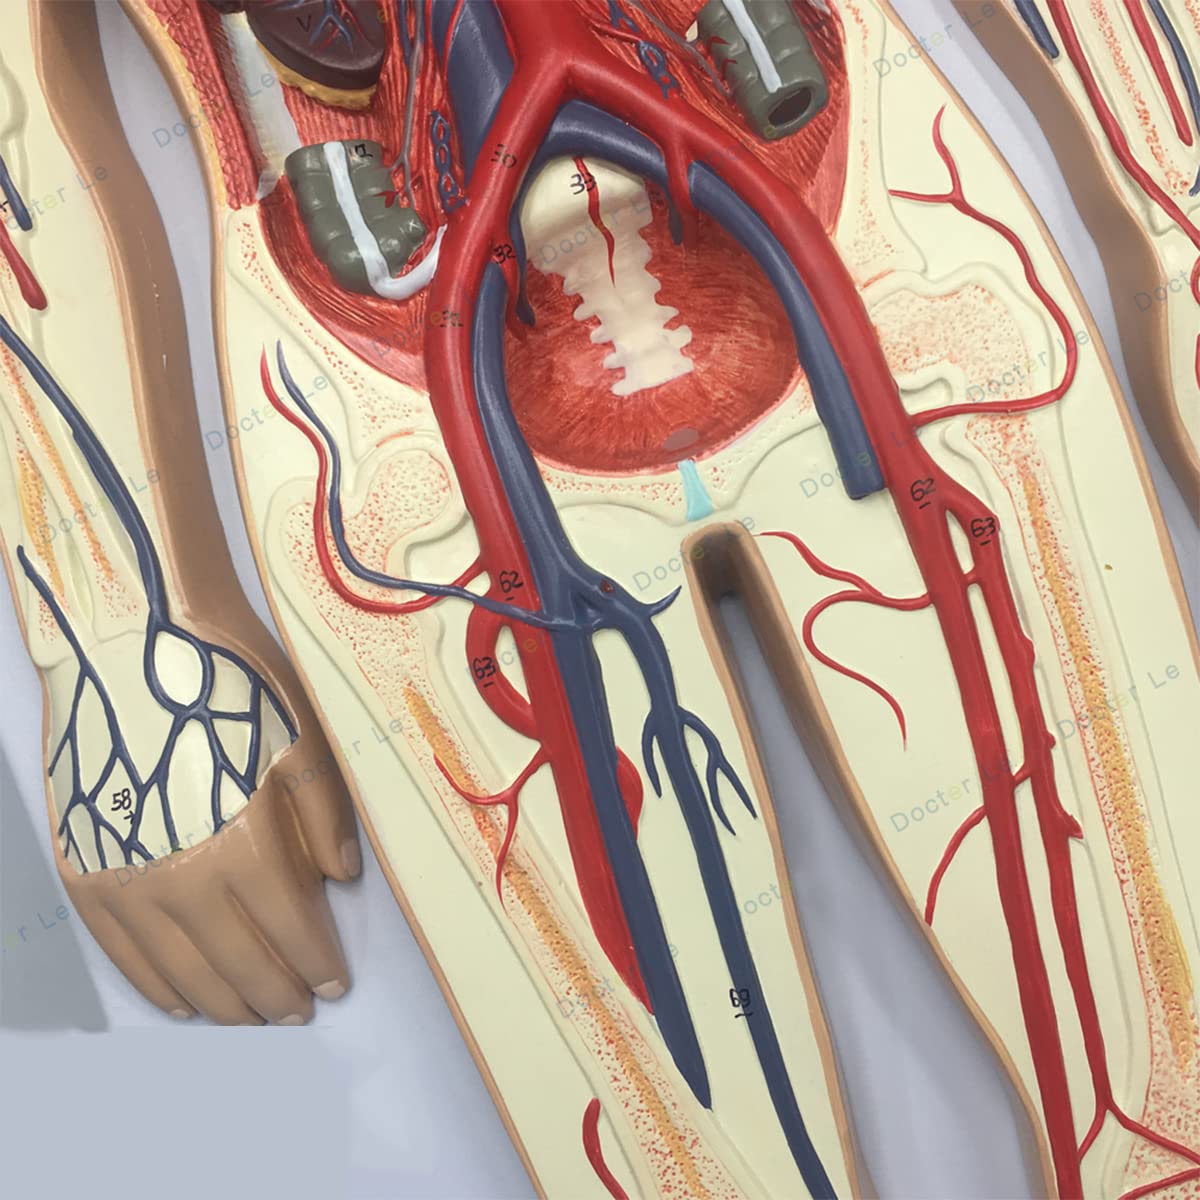

- Features: This model shows the structure of blood circulation in various parts of the human body. The circulatory system is the channel through which blood flows in the body and is divided into two parts: the cardiovascular system and the lymphatic system. Blood circulation route: superior and inferior vena cava → right atrium → right ventricle → pulmonary artery - → alveolar surrounding → pulmonary veins - >> left atrium → left ventricle → aorta - → systemic tissues (except lung). Product Size: Using this model helps to understand the composition and structure of human blood circulation. The size of the model is 1/2 the size of the human blood circulatory system. Product size: 90*30 cm/35.4*11.8 inches. High Quality: High-quality prototypes, sturdy hand-made, not fragile, made of high-quality environmentally friendly PVC, fine workmanship, creating good objects with clear shapes and rich details. Meticulous workmanship: The model has meticulous workmanship, realistic details, clear texture, easy to use and easy to observe. This product comes with a base, which is convenient for learning and teaching. Good Teaching Aids: This collection is designed for anatomy professionals and students. We are sure you will love these models. Can also be given as a gift to educators or doctors, excellent educational tool for students/teachers/professionals.